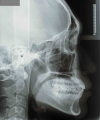

カテゴリー: ClassⅢ malocclusion(非抜歯症例)

出題基準:大臼歯関係がclass Ⅲで、少なくとも前歯部が反対咬合または切端咬合で、ANB 0度以下が望ましい。

初診時